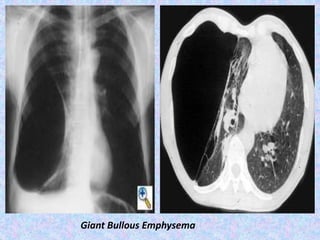

Giant Bullous Emphysema

CT finding in emphysema is diagnosed by alveolar septal destruction and

airspace enlargement, which may occur in a variety of distributions.

Centrilobular emphysema is predominantly seen in the upper lobes with

panlobular emphysema predominating in the lower lobes. Paraseptal

emphysema tends to occur near lung fissures and pleura. Formation of giant

bullae may lead to compression of mediastinal structures, while rupture of

pleural blebs may produce spontaneous pneumothorax /

pneumomediastinum.